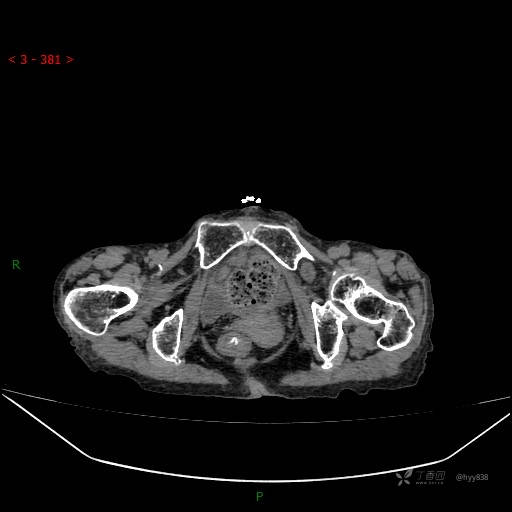

夜班急诊经典病例分享。老年女性,突发腹痛就诊,请讨论……结果公布~

主诉 :腹痛14小时

现病史: 家属诉患者于14小时前出现腹痛,伴有肛门停止排气排便,不伴有畏寒、发热、恶心呕吐、腹泻等不适,患者家属为求进一步治疗,就诊于我院急诊科,门诊以腹痛待查收入院, 起病以来,患者精神、睡眠差,进食少,小便正常,大便未解,近期体力、体重无明显下降。

腹部CT平扫